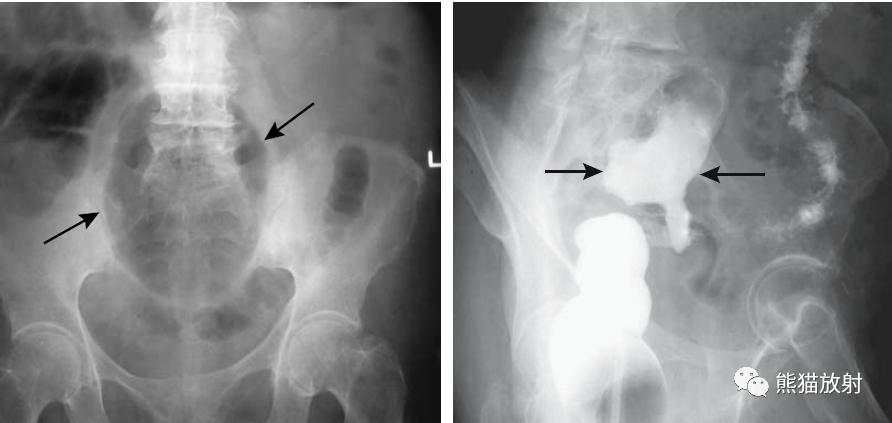

巨大的乙状结肠憩室。X线平片示盆腔巨大充气结构(箭头)。钡灌肠确定为憩室(箭头),并与结肠相连。